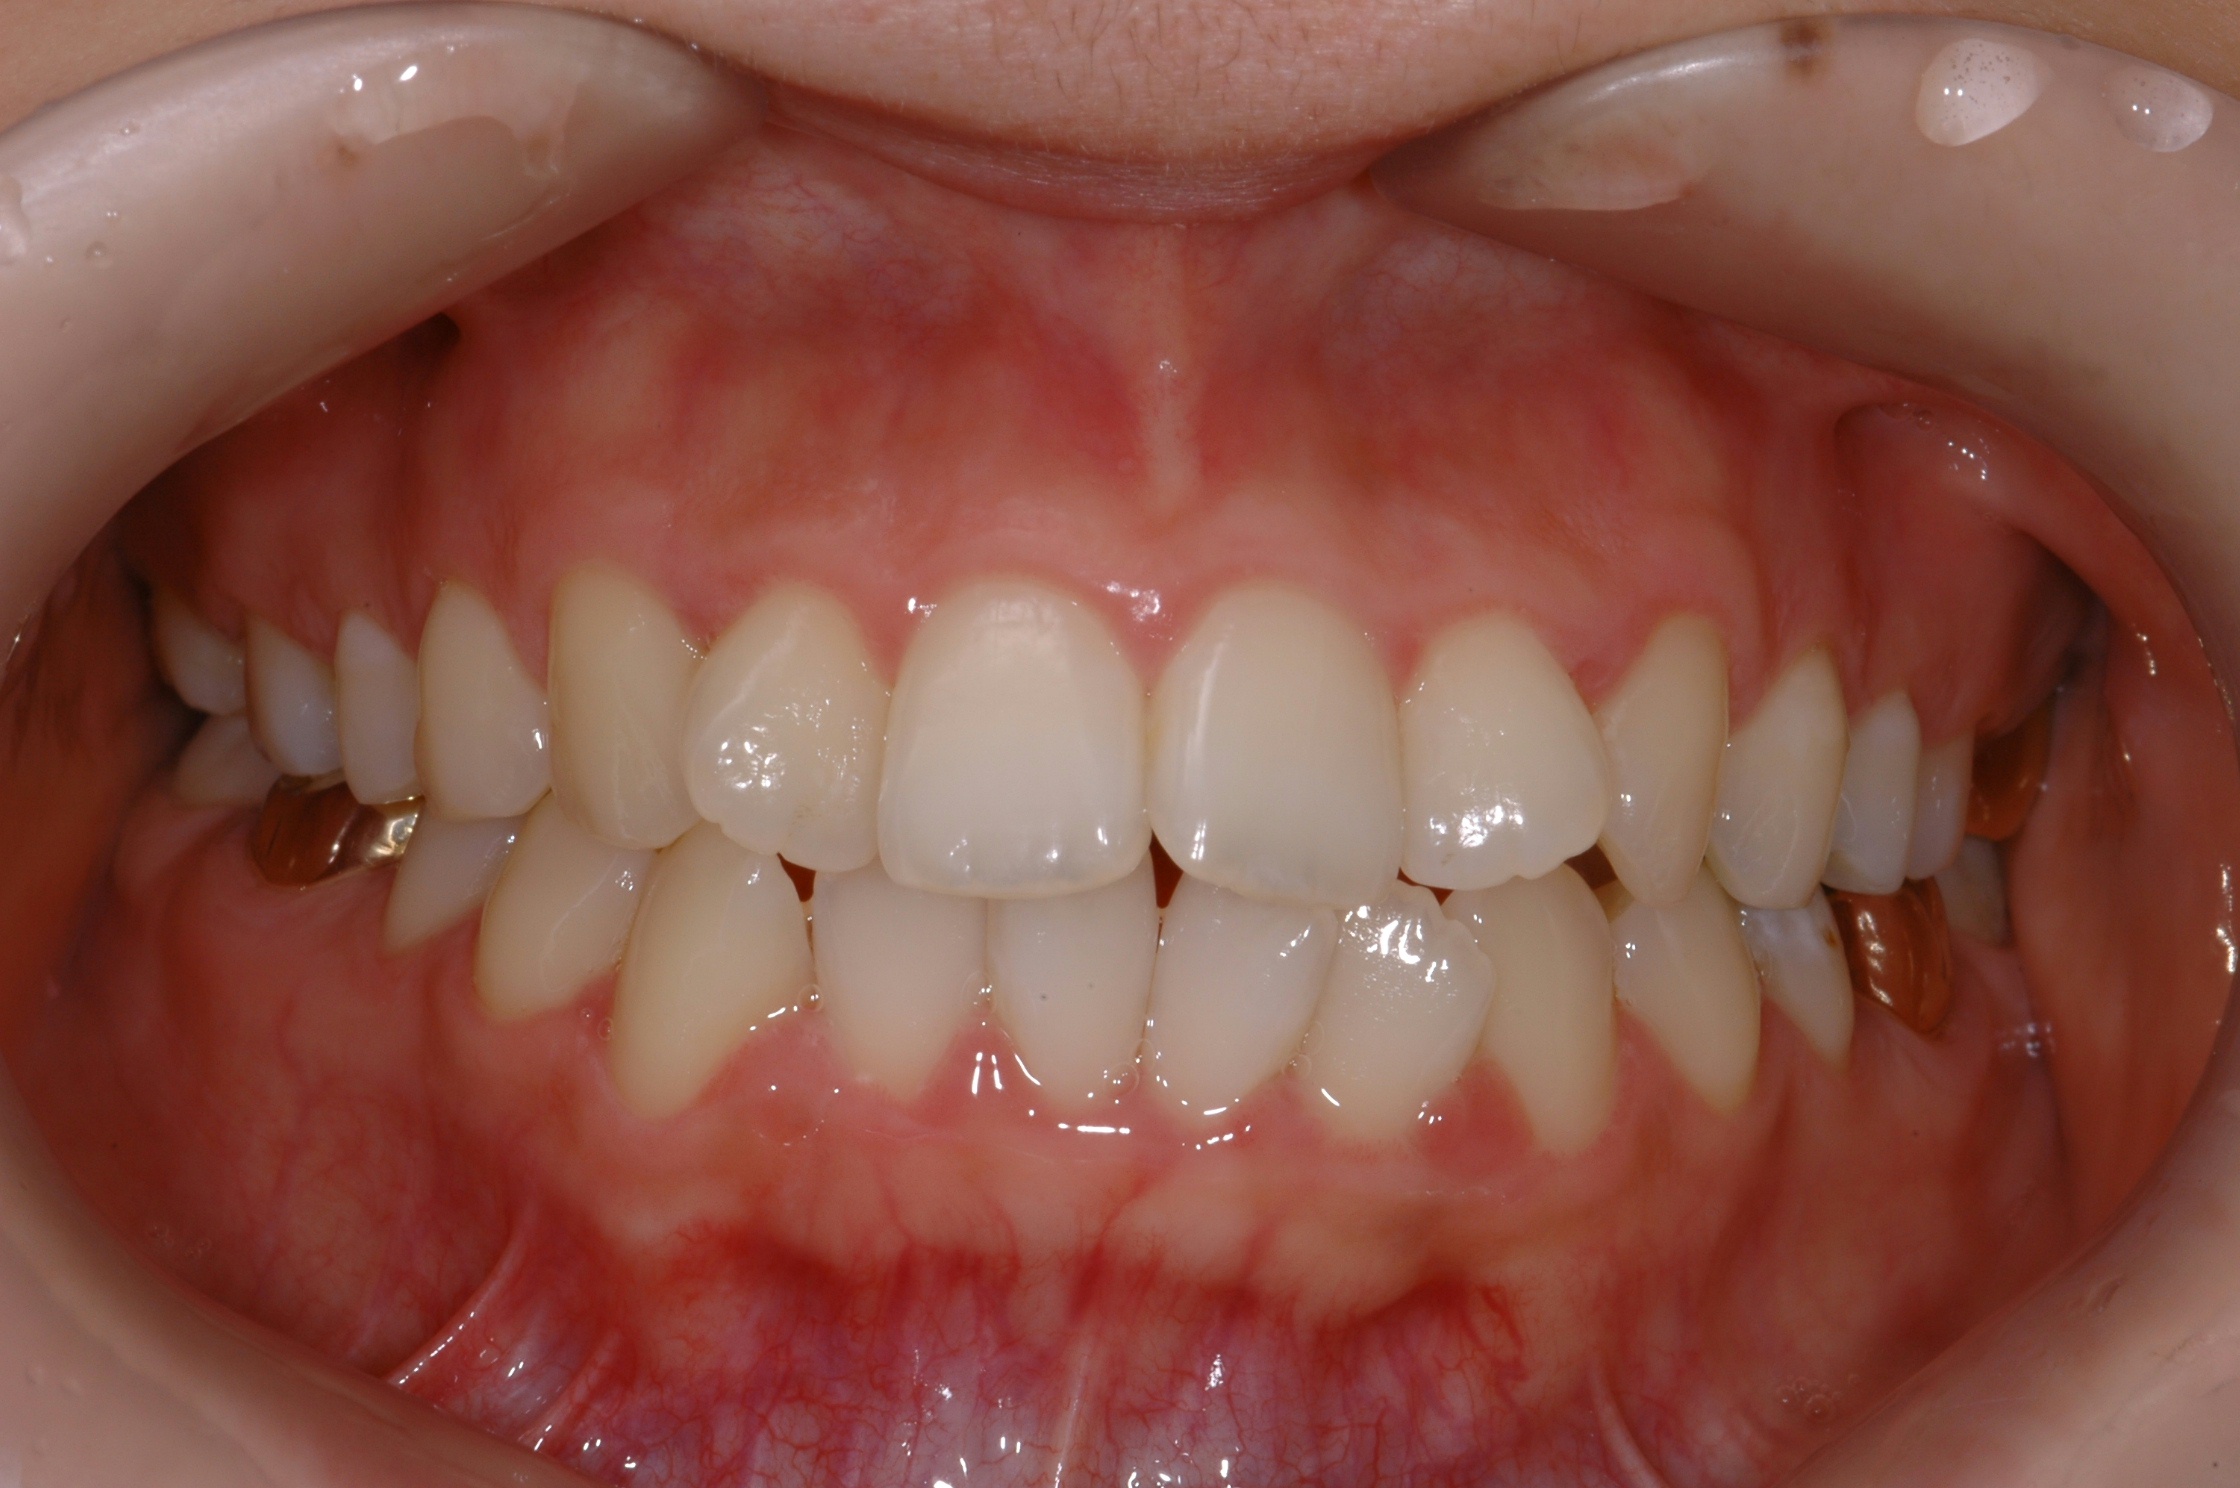

치료 전 사진입니다.